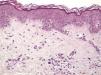

The essential feature of a melanocytic nevus undergoing spontaneous regression is the replacement of tumor cells by a fibrous stroma with varying degrees of inflammation and new blood vessel formation as well as varying numbers of melanophages (Fig. 1).7,19 From an exclusively histologic perspective, it is very difficult to determine the biology of a lesion after complete regression and in most cases only the later detection of metastasis on follow-up allows distinctions to be made.

Histologic observations (Table 2) are exemplified in Figs. 2–6.

The clinical and dermoscopic features of the melanocytic nevi we analyzed revealed characteristic patterns. Clinically, these nevi involuted very rapidly. On histology, extremely thin collagen bundles were seen to have created a particular pattern of fibrosis referred to as delicate (Fig. 3). In all our cases, dermoscopy confirmed complete involution of the nevus within a much shorter period (mean of 6.4 months) than is observed in halo nevi. Loss of structure and the presence of multiple pepper-like granules (which is correlated with a histologic finding of melanophages) were the main dermoscopic findings (Fig. 8). In most cases, the morphologic features of the residual lesion were very similar to those seen in lichenoid keratosis. Although follow-up was not long in our series (ranging between 1 and 3 years), there were no cases of metastasis.

Immunohistochemistry confirmed the complete absence of nevus cells in these cases. Our observations included melanophages (Fig. 4), present in varying degrees and extensive in only 2 cases; inflammatory infiltrates (Fig. 5), mild or moderate in most cases; vascular proliferation (Fig. 3); and a particular type of fibrosis consisting of fine collagen bundles that were often located subepidermally (Fig. 3) and that have not been described in halo nevi or melanomas to date. In melanoma, fibrosis is usually dense but in halo-nevus formation it does not develop in the final stages. Fibrosis is generally a less significant finding in conventional nevi undergoing spontaneous regression than it is in regressing melanomas; an exception is the sclerosing nevus with pseudomelanomatous features that has recently been described.42–45 Such nevi are trizonal, consisting of an area of proliferating atypical melanocytes with pagetoid spread, an area of significant dermal sclerosis containing irregular nests of melanocytes, and an area of residual nevus tissue around and below the scar. Structural changes in these melanocytic neoplasms are usually so pronounced that they sometimes lead to a diagnosis of melanoma with regression or nevus-associated melanoma with regression. Nonetheless, the cytologic criteria essential for a diagnosis of melanoma are not met in most of these cases and to date complete regression has not been reported.

Delicate fibrosis, such as we observed in the nevi in this series, can be distinguished from the laminar fibrosis typical of a dysplastic nevus because parallel and/or concentric fibrotic bundles will not be present. Instead, thin collagen fibers will be scattered in the lesions and cellularity will be reduced and without signs of significant activation. In the absence of activation, the lesion can be considered stable and at the end of the fibrotic process, which will not continue on toward more organized patterns (as in a dysplastic nevus) or thickened bundles (as in melanoma regression). Therefore, we conclude that even though we removed the nevi within a very short period (in less than 2 weeks of noticing the changes), a biopsy performed at a later date would not have shown laminar fibrosis or thick bundles. The process would more likely have abated and the tissue would probably have been more similar to normal skin.